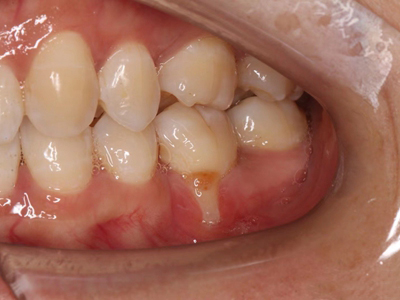

牙龈退缩牙龈萎缩露出牙根图

牙龈退缩发作于上排尖牙和磨牙处,导致牙根暴露在外,伴有牙齿松动、口臭、牙根面敏感等症状,是由于刷牙不当、牙周炎等因素引起。